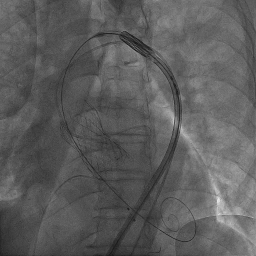

入路检查

术后患者恢复好,复查超声:

LVEF:57%,LVEDD:62mm,LVESD:43mm,主动脉瓣功能正常,瓣周漏(少量),二尖瓣中度反流,三尖瓣中度反流。